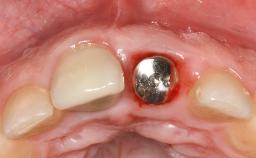

Late Presentation of Peri-Implant Mucositis Requiring Soft-Tissue Augmentation and Esthetic Crown Lengthening at Implant Site 11

Biological or technical complications around implant-supported prostheses place a significant burden on patients as well as the surgical and restorative team. Inflammation of the peri-implant soft tissues is often the first sign that something has gone awry. While there is never a good time for a complication, late presentation of inflammation in the soft tissues around a long-standing prosthesis triggers a period of research and review of the case in order to ascertain the treatment history and its possible contribution to the etiology of the situation. This becomes more complicated in situations where a patient has not received regular maintenance and clinical/radiographical examinations due to personal, financial, or professional reasons. When the complication occurs in the esthetic zone, the complexity of the situation expands exponentially, as the only acceptable outcome in the patient’s eyes will be the maintenance of the esthetics of the prosthesis.